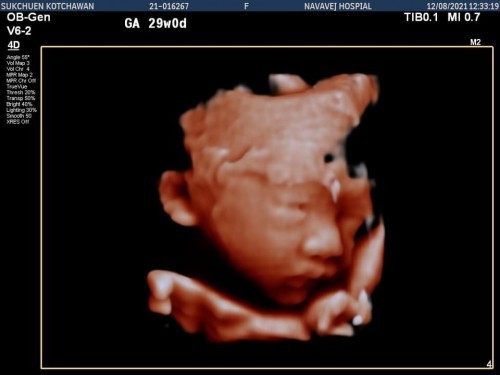

ตอนนี้ตั้งครรภ์ได้36สัปดาห์5วันแล้วค่ะ 🎉 นี้เป็นท้องแรกถือเป็นประสบการณ์ใหม่ในชีวิตของผู้หญิงคนนึง ตอนรู้ว่าท้องไตรมาสแรกเหม็นอาหารและกินข้าวไม่ค่อยได้ และของโปรดที่ชอบอยากส้มตำก็กินไม่ได้ 🤣อ้วกหนักมาก จนน้ำหนักลด 😭ทำให้เป็นห่วงเจ้าตัวเล็กในท้องมาก เป็นช่วงที่ศึกษาหาข้อมูลเยอะมาก พอเข้าไตรมาสที่สองอาการแพ้ท้องก็หายไป เริ่มร่าเริง มีความสุขในการตั้งครรภ์และการกิน ส่วนตอนนี้เข้าไตรมาสที่3เรียบร้อยค่ะ อาการตอนนี้ทำอะไรจะเหนื่อยง่าย และเข้าห้องน้ำบ่อยมาก😅ลางานอยู่บ้านเตรียมคลอดแล้วค่ะ✌️✌️✌️ ฉีดบาททะยักครบ3เข็มเรียบร้อย ส่วนวัคซีนโควิด💉ตอนแรกก็ว่าจะฉีดหลังคลอด แต่ที่ทำงานอยากให้ฉีดมาก เลยหาข้อมูลกับแฟนจนตัดสินใจฉีดไฟเซอร์ค่ะ เพิ่งฉีดเข็ม2วันที่4ต.ค ไป เข็มแรกมีอาการแค่ง่วงนอน ส่วนเข็ม2แขนข้างที่ฉีดมีอาการปวดเล็กน้อย ลูกยังดิ้นปกติดีค่ะ ส่วนใหญ่จะชอบดิ้นตอนกลางคืน😊น้ำหนักจาก45ตอนนี้62เป็นที่เรียบร้อย ส่วนเพศลูก เป็นผู้ชายคร้า 👶🏻 🌈กำหนดคลอด28ตุลาคมค่ะ #เลยอยากถามแม่ๆว่าส่วนใหญ่จะคลอดกันตอนกี่สัปดาห์ค่ะ ตอนนี้ตื่นเต้นและอยากแตกมากเลยค่ะ ใครมีประสบการณ์อยากแชร์ให้กันฟังได้เลยนะค่ะ 😍 ขอเป็นกำลังใจให้แม่ๆที่กำลังตั้งครรภ์ทุกคนนะค่ะ😘สู้ๆๆ